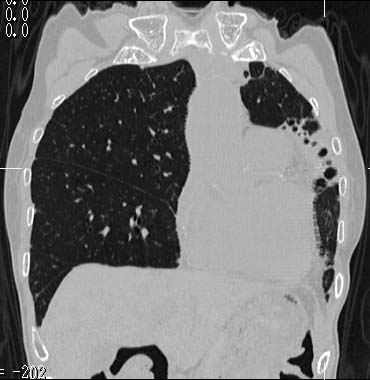

MPR

Data acquired & processed by R. Kato M.D.